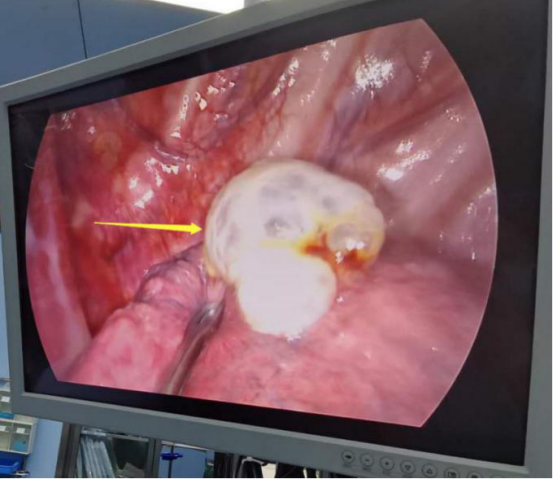

手术过程中。

患者肺大泡明显,术后切口较小。